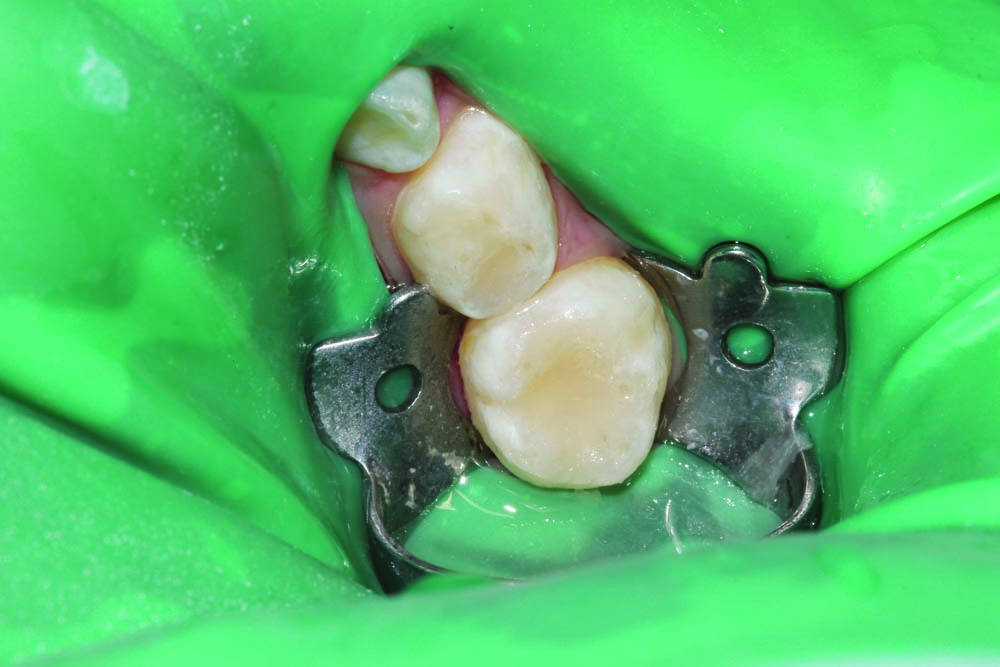

A 3-year-old patient presented with multiple carious lesions in all quadrants. Dental restorations were carried out with patient under general anesthetic. Quadrant 4, teeth #84 (S) and #85 (T) each were cavitated on the occlusal surface into dentin (Fig. 1).

The quadrant was isolated with an 8A ivory clamp and slot-style rubber dam, and a conservative outline was prepared using an NSK high-speed handpiece and a 330 FG bur. Caries was excavated with an NSK slow-speed handpiece and 6 and 8 round burs (Fig. 2) followed by a selective-etch technique with phosphoric acid (Fig. 3).

Futurabond U was applied to the preparation and the entire occlusal surface (Fig. 4). Teeth were restored with Admira Fusion by Voco, an all-ceramic-based universal restorative material, then shaped and light-cured before a final layer of Admira Fusion Flow was placed over the entire occlusal surface to act as a sealant for any additional pits and fissures on the occlusal surface, as seen in the final completed restorations (Fig. 5).